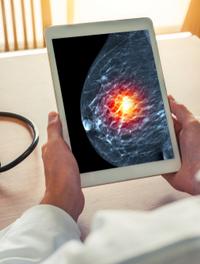

Depuis la mise en place du dépistage systématique et l’avènement des radiographies numérisées, l’incidence du carcinome canalaire in [...]